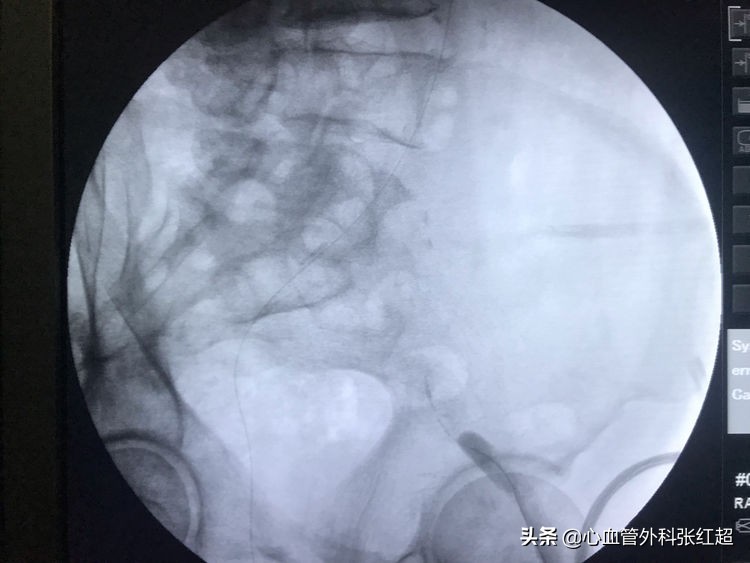

导丝进入假腔方向,加用微导管,换导丝破膜入真腔。

方位验证导丝入真腔后,用微导管造影进一步验证。